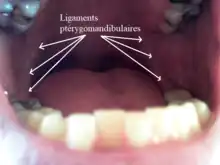

Le ligament ptérygo-mandibulaire est une structure paire formée par le fascia bucco-pharyngé[2], un ligament de chaque côté. Sa face médiale est recouverte par la muqueuse buccale (en) de la bouche. Sa face latérale est séparée de la branche de la mandibule par une quantité de tissu adipeux. Ses bords antérieur et postérieur donnent insertion au muscles buccinateur et constructeur supérieur du pharynx respectivement[3].

Chez les fœtus, le raphé ptérygomandibulaire est toujours très proéminent. Cependant, chez les adultes, il peut devenir moins distinctif. Il est très grand et distinctif chez environ 36 % des adultes[4].